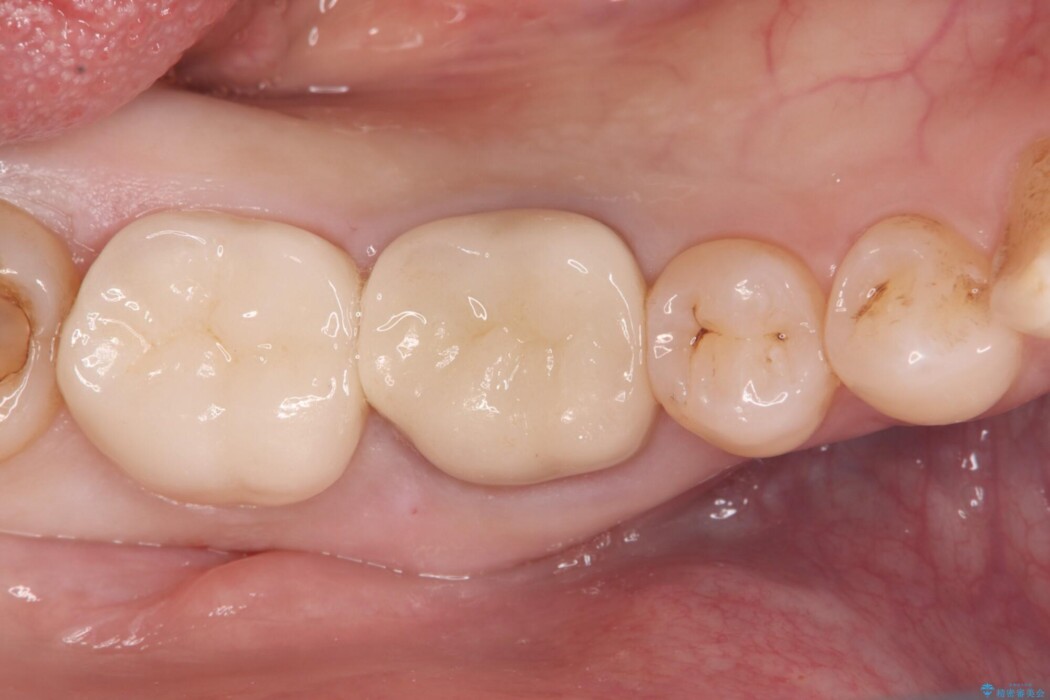

古い銀歯と中の虫歯をしっかりと取り除き、耐久性の高いセラミッククラウンで補強しました。

型取りには精密なシリコン材を使い、細菌の再侵入を防ぎます。

セラミックは見た目が美しいだけでなく、汚れがつきにくく、良好な口腔衛生状態を維持しやすくなり長期的に安心して使用できる状態へと整えることができました。